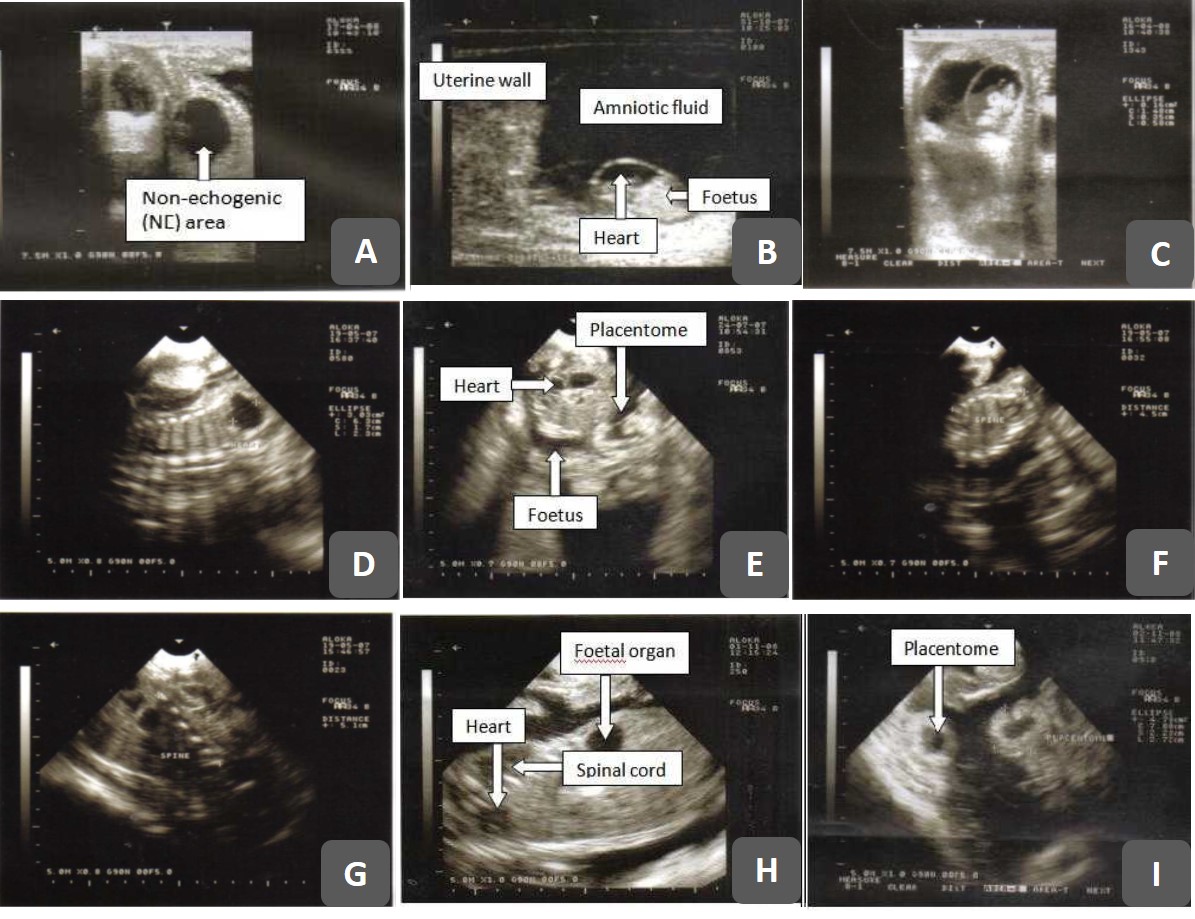

From vetsciencereview.blogspot.com

Ultrasonography (Usg) dan Aplikasinya Pada Pemeriksaan Organ Reproduksi Ut L Pada Usg Selamat malam dokter, saya ingin bertanya saya ada test usg transvaginal hasilnya : Limpa, yaitu organ yang berada di perut kiri atas bersebelah dengan lambung. Urinary track atau saluran kemih. Usg transvaginal atau disebut dengan usg endovaginal ini, biasanya direkomendasikan dokter untuk mendeteksi kondisi abnormal pada rahim atau mengecek kesehatan janin. Usg selama kehamilan penting agar anda bisa mengetahui pertumbuhan. Ut L Pada Usg.